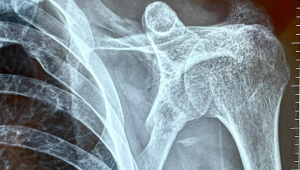

医生会根据骨折的愈合情况,如通过影像学检查(如 X 光、CT等)来确定骨折部位是否已经完全愈合,骨痂的生长是否坚固等。还会对肩部及上肢的肌肉力量、关节稳定性等进行详细的检查和评估。只有当各项指标都显示身体具备了一定的运动能力和承受能力时,才可以在专业人士的指导下,谨慎地开始尝试一些轻度的足球相关活动,如简单的传球、带球练习等。但在这个过程中,一定要密切关注身体的反应,如果出现疼痛、不适等症状,应立即停止运动,并及时就医。